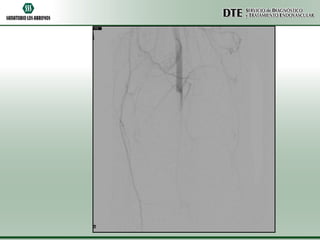

Arteriografía MMII

Arteriografia MMII

•Conclusiones:

•Oclusión completa de arteria poplítea izquierda

•Oclusión de arteria tibial posterior derecha

•Conclusiones: •Oclusión completa dearteria poplítea izquierda •Oclusión de arteria tibial posterior derecha